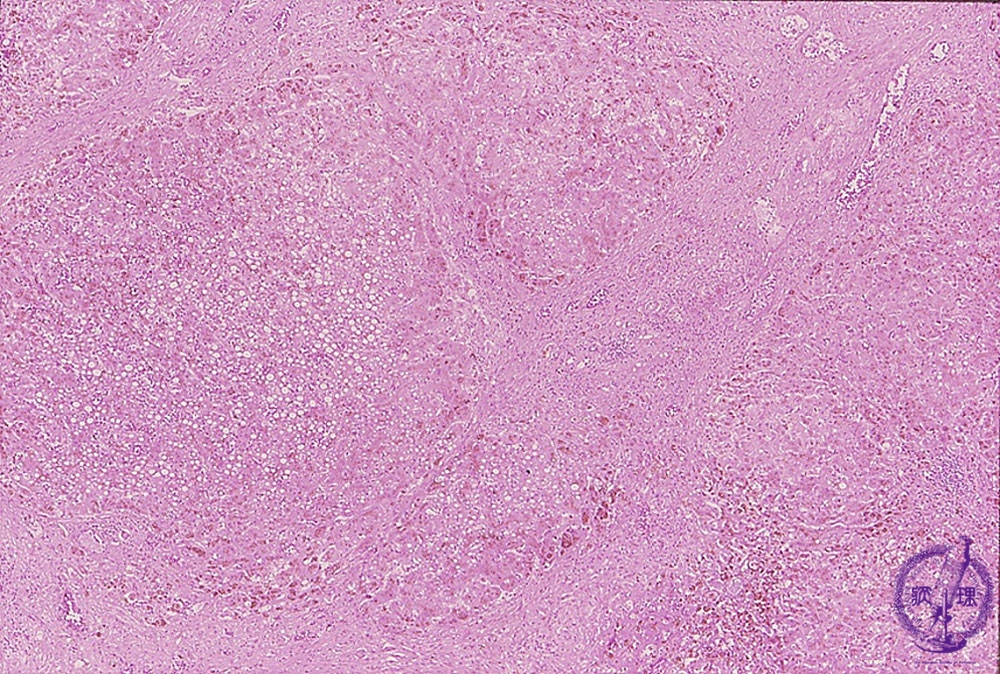

- 10.Liver

- (9)Liver hemochromatosis

Microscopic finding (HE stain, low power view): Regenerative nodule formation is accompanied by severe fibrosis with cirrhosis. Areas around regenerative nodules have a brownish tone due to hemosiderin deposition.